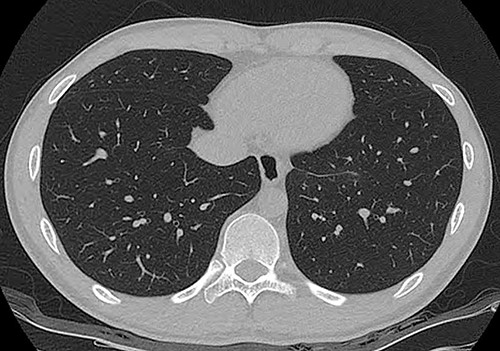

An 18-year-old male patient presented to the emergency department with right-side chest pain of 1-day duration. A plain chest x-ray confirmed a right pneumothorax. A tumor in the left lower paravertebral area was suspected (Fig. 1a). A CT of the chest was performed and showed a 6-cm large, well-defined, probable cystic mass in the left posterior mediastinum, adjacent to the esophagus. Esophageal duplication or bronchogenic or neurenteric cyst was suspected (Fig. 1b and c). The patient was discharged after pneumothorax had improved. Two months later, he was readmitted for surgery to remove the cystic tumor. Single-incision video-assisted thoracoscopic surgery (VATS) was performed to treat the posterior mediastinal tumor. The patient was placed in the prone position. An incision of 4 cm in length was made in the left ninth intercostal space at the lateral line of the scapula. A 5-mm thoracoscope with a 30-degree view was used. A cyst was identified in the posterior mediastinum (Fig. 2a), and a longitudinal incision was made in the mediastinal pleura. The left vagus nerve was placed beside the tumor. The lower half of the cystic mass was embedded in the muscular layer of the esophagus (Fig. 2b) and was in contact with the esophageal mucosa. The cyst was dissected carefully from the surrounding tissue. During dissection, the cyst ruptured, discharging an ivory mucoid creamy fluid. The cyst was completely removed with no injury to the esophageal mucosa. The esophageal mucosa, which was in close contact with the cyst, was stretched and protruding. To cover the exposed esophageal mucosa, the dissected esophageal muscle and periesophageal tissue were approximated with a continuous suture using a barbed suture (V-Loc™ 90, Medtronic) (Fig. 2c). Another barbed suture was used to repair the mediastinal pleura. A 24-Fr chest drain tube was placed through the same port (Fig. 2d). The operation took 80 min. The patient’s diet was started on the evening of the surgery. The chest drain was removed on the 1st postoperative day, and the patient was discharged from the hospital on the 2nd postoperative day without problems. Histopathological examination revealed a bronchogenic cyst. A CT scan of the chest carried out 2 years 7 months after the operation and confirmed that the patient had healed without any complications (Fig. 3).

A computed tomography scan at 2 years 7 months after surgery. There was no evidence of tumor recurrence.